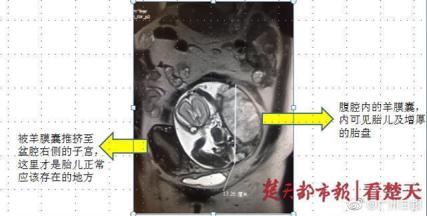

昨天,《楚天都市报》报道了这样一则新闻——湖北有位宫外孕的孕妇,为了保住输卵管和胎儿,不去做手术,结果胎儿在腹腔内生长,目前已经妊娠26周了。

新闻里的孕妈的情况是属于腹腔妊娠,常常发生在输卵管妊娠流产或破裂后,存活的胚胎绒毛组织重新种植到腹腔中生长。